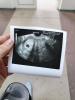

У кого были истории, что на моем сроке еще не визуализируется ПЯ в матке?

По узи не нашли. Еду сдавать хгч.

Боязно, что может быть внематочная.

Заодно проверила рубец ❤️

Была поздняя овуляция, в 7 недель увидели только пя пустое, в 8 недель уже был эмбрион и пульсация,в 10 недель сердцебиение и срок поставили 8 недель

Мне и на 6 неделе не увидели ПЯ, сказали ЖТ есть , а ПЯ вообще не визуализируется ) через неделю повторно сделали и все нормально было 😌

Ой ,они в 5 недель всем внематочные ставят ,вот мои две внематочные ,рано больше на узи не хожу